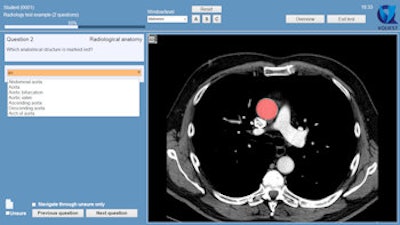

Example of a question in which students are asked to name the marked structure. In this case, they need to choose from a long list of options, which they can only open by typing at least two letters of their answer. All alternatives including these two letters are then shown, and the student can click on the preferred answer. This allows for automatic answer checking.